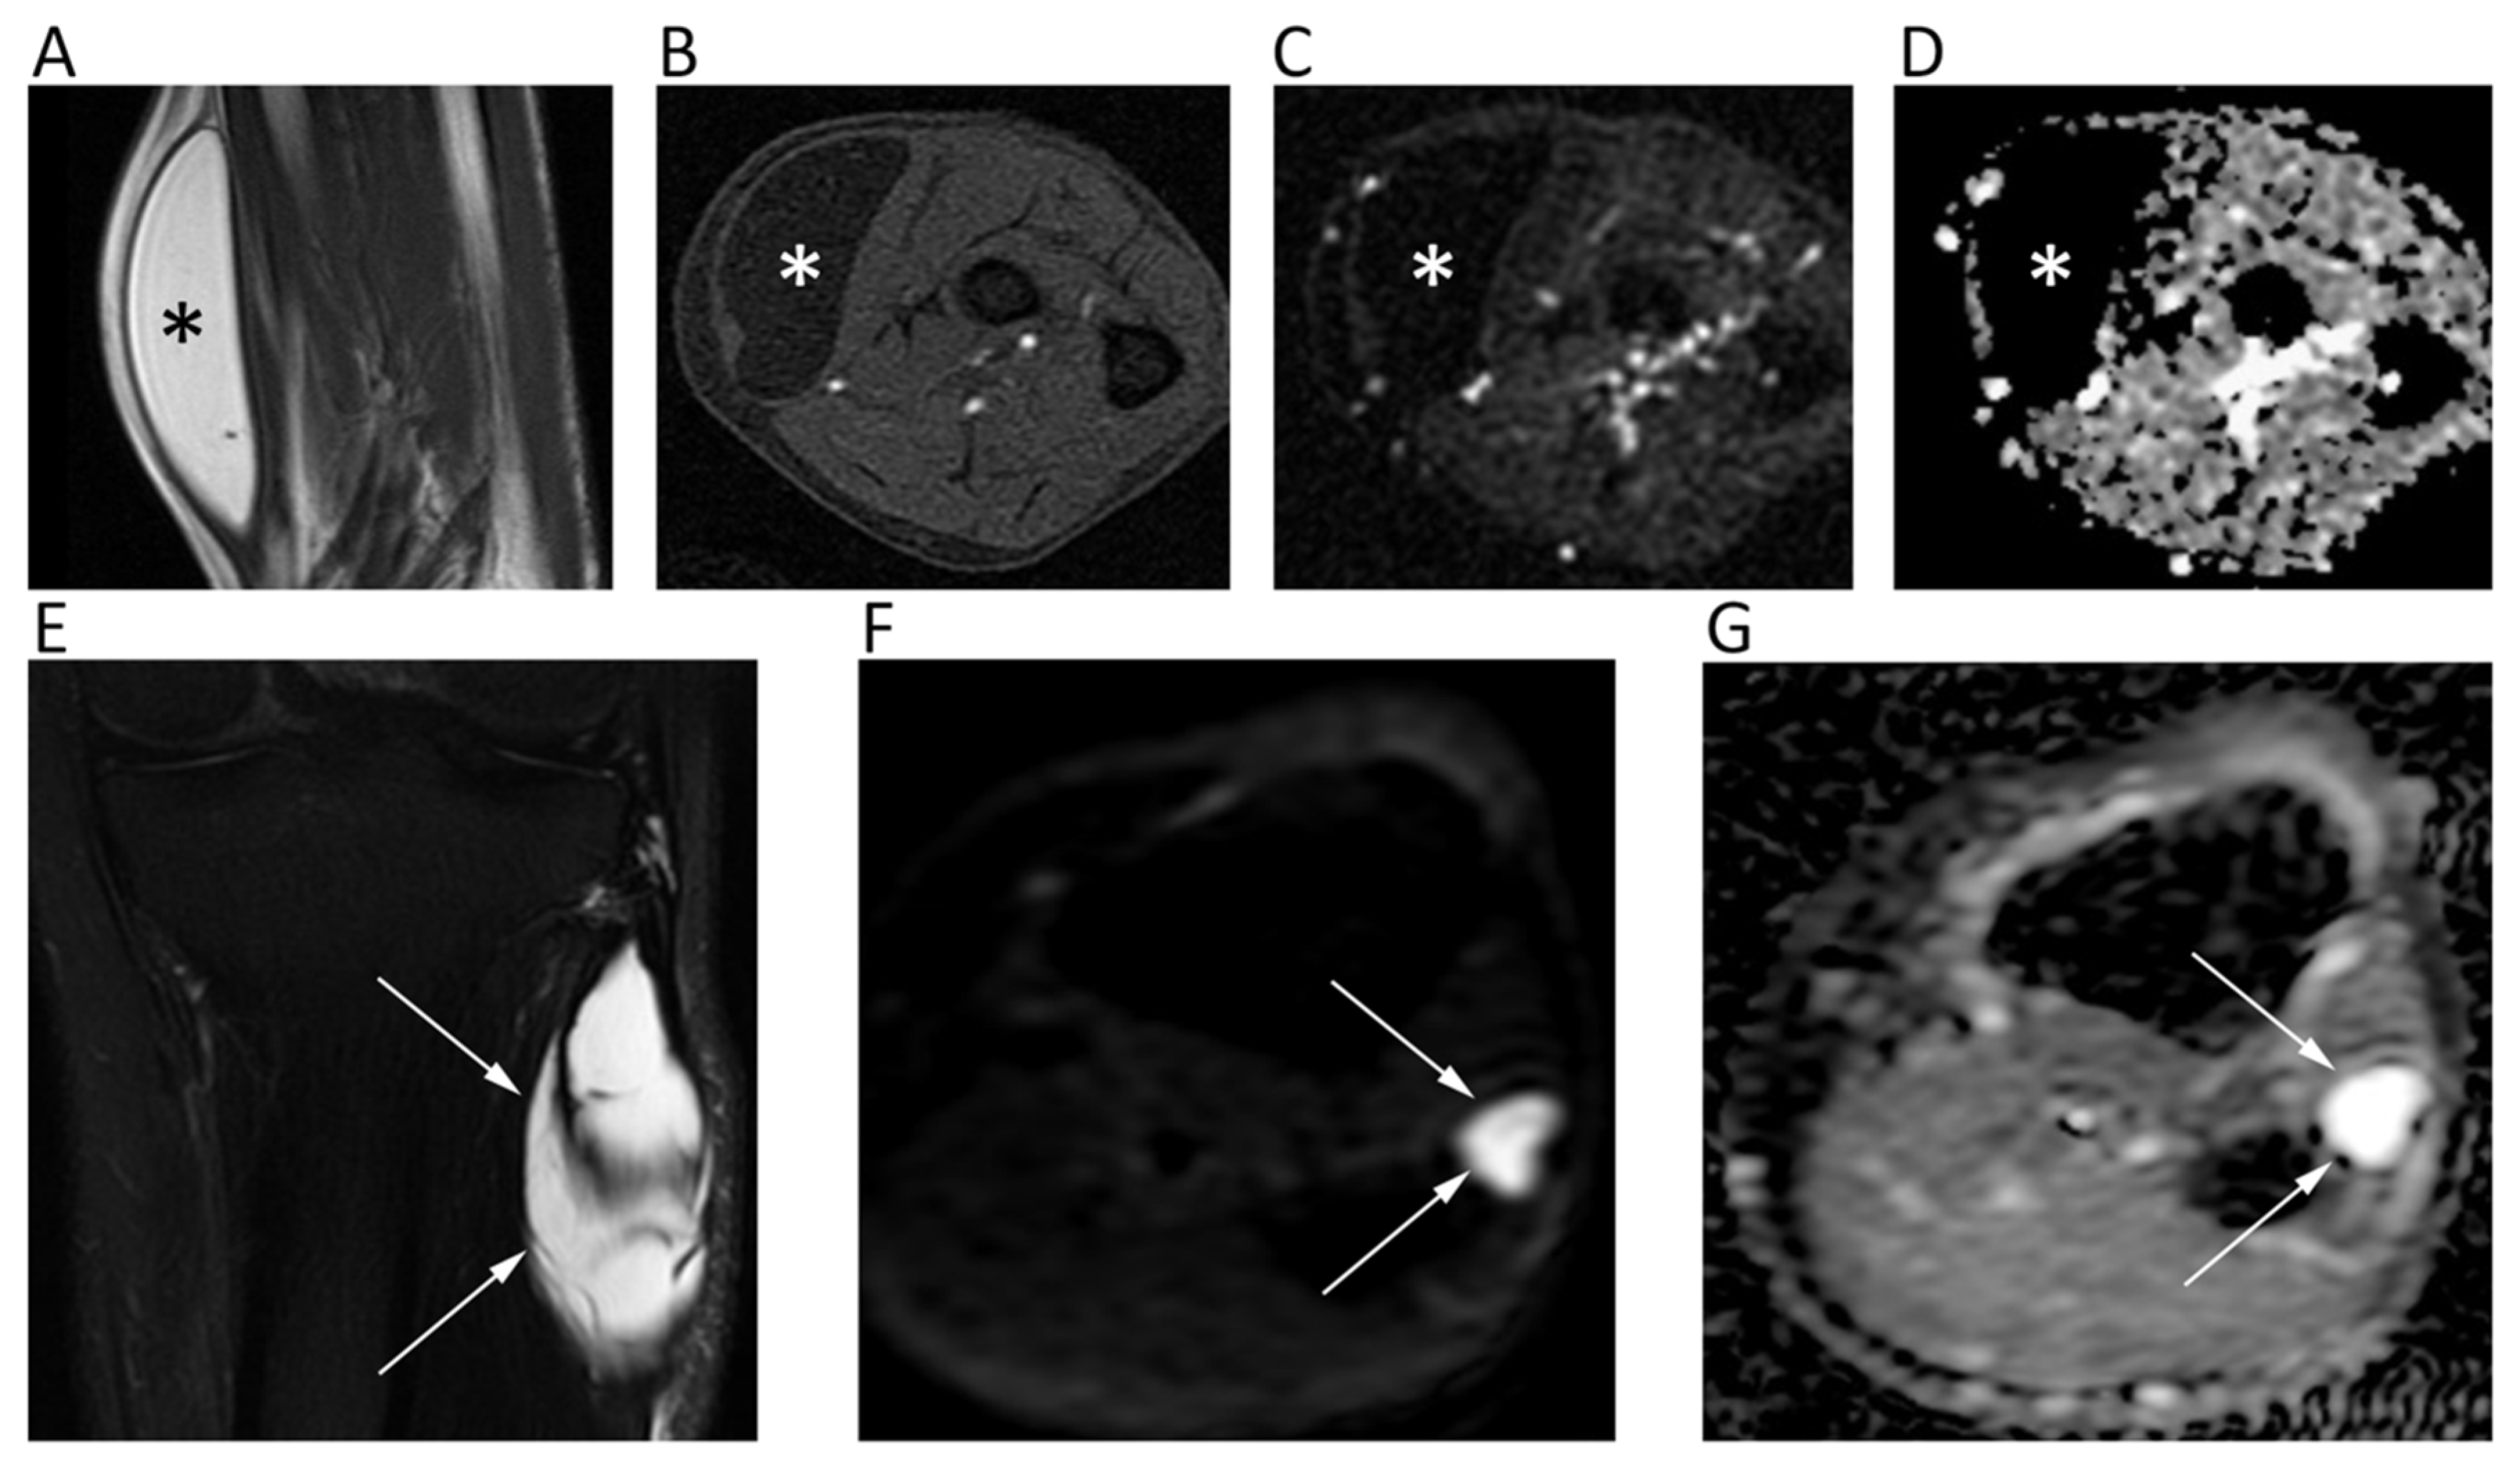

13. Bone Tumors

14. Soft Tissue Tumors

- Robba, T.; Chianca, V.; Albano, D.; Clementi, V.; Piana, R.; Linari, A.; Comandone, A.; Regis, G.; Stratta, M.; Faletti, C.; et al. Diffusion-weighted imaging for the cellularity assessment and matrix characterization of soft tissue tumour. Radiol. Med. 2017, 122, 871–879. [Google Scholar] [CrossRef]

- Subhawong, T.K.; Jacobs, M.A.; Fayad, L.M. Insights Into Quantitative Diffusion-Weighted MRI for Musculoskeletal Tumor Imaging. AJR Am. J. Roentgenol. 2014, 203, 560–572. [Google Scholar] [CrossRef]

- Choi, Y.J.; Lee, I.S.; Song, Y.S.; Il Kim, J.; Choi, K.-U.; Song, J.W. Diagnostic performance of diffusion-weighted (DWI) and dynamic contrast-enhanced (DCE) MRI for the differentiation of benign from malignant soft-tissue tumors. J. Magn. Reson. Imaging 2019, 50, 798–809. [Google Scholar] [CrossRef]

- Bruno, F.; Arrigoni, F.; Mariani, S.; Splendiani, A.; Di Cesare, E.; Masciocchi, C.; Barile, A. Advanced magnetic resonance imaging (MRI) of soft tissue tumors: Techniques and applications. Radiol. Med. 2019, 124, 243–252. [Google Scholar] [CrossRef]

- Del Grande, F.; Subhawong, T.; Weber, K.; Aro, M.; Mugera, C.; Fayad, L.M. Detection of Soft-Tissue Sarcoma Recurrence: Added Value of Functional MR Imaging Techniques at 3.0 T. Radiology 2014, 271, 499–511. [Google Scholar] [CrossRef] [PubMed]